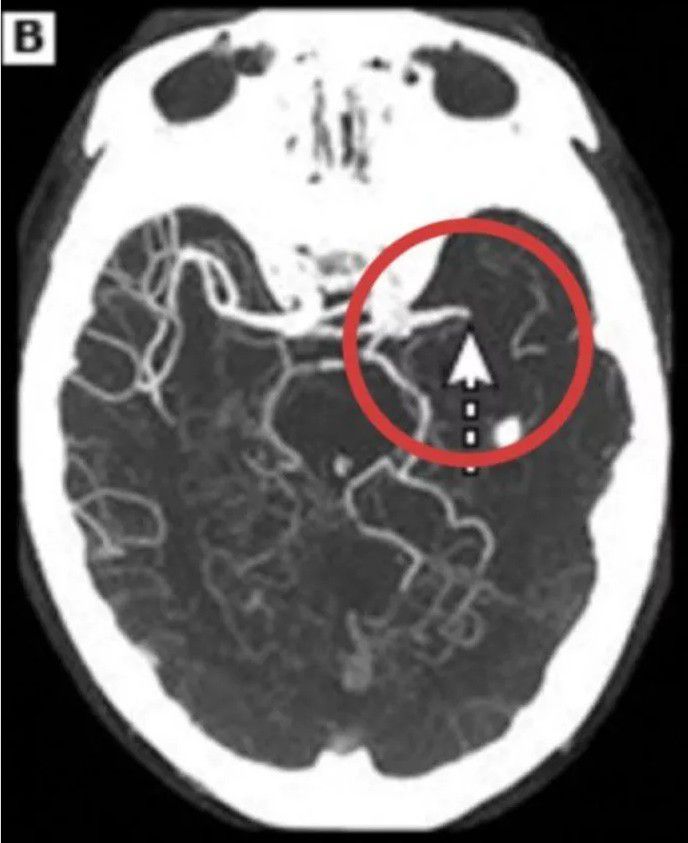

Surgical Clipping Of Brain Aneurysms